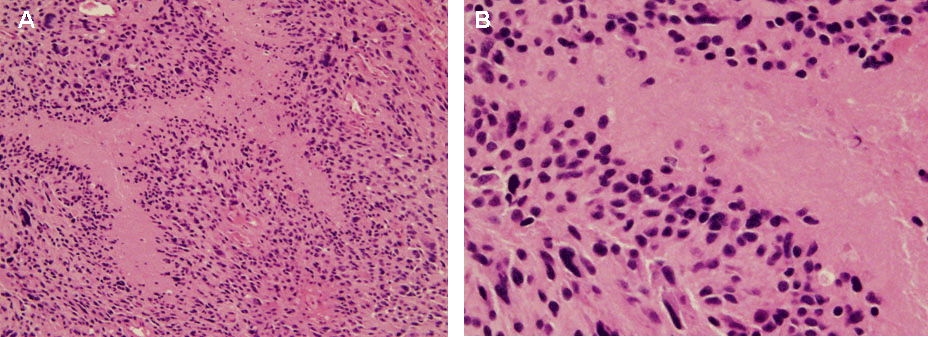

| Figure 4: Distinguishing cellular features of GBM. One of the distinguishing features of GBM compared to lower grade gliomas is the extent of tissue necrosis within the tumor mass. H&E stains of tumor tissue at 20X (A) and 40X (B). Pseudopalisading cells surrounding the necrotic foci, a feature suggestive of the poor prognostic nature of GBM, can be observed. |